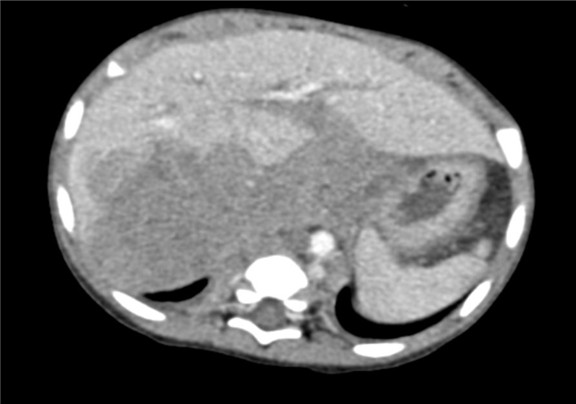

下腹部增强CT示:右肾上腺区占位并周围侵犯,腹腔、腹膜后多发淋巴结肿大,考虑恶性肿瘤,神经母细胞瘤?胆囊炎可能性大。

术前CT检查:

动脉期

静脉期

平衡期